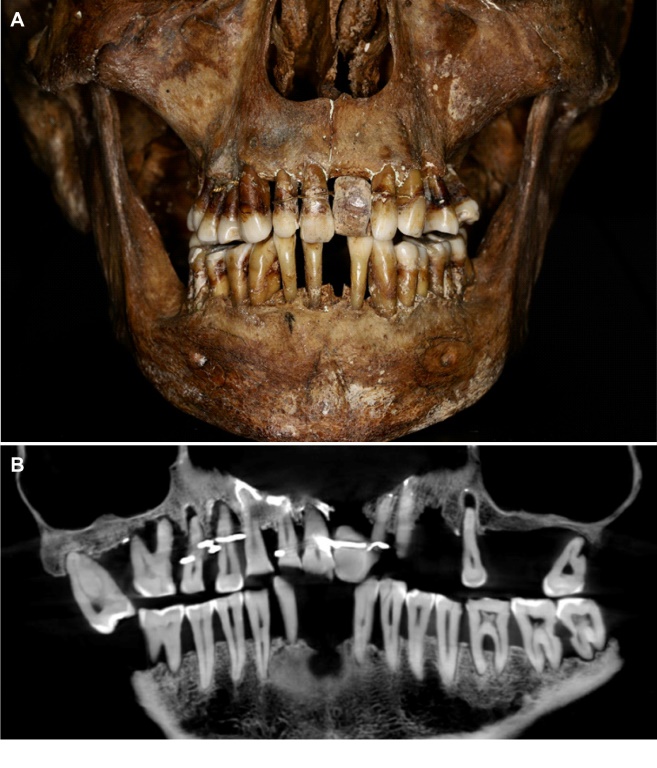

The teeth of 17th century French aristocrat Anne d'Alegre, with a gold wire threading through several

Embalmed in a lead coffin, her skeleton -- and teeth -- were remarkably well preserved.

Thirty-five years later, a team of archaeologists and dentists have identified that d'Alegre suffered from periodontal disease that was loosening her teeth, according to a study published in the Journal of Archaeological Science: Reports this week.

A "Cone Beam" scan, which uses X-rays to build three-dimensional images, showed that gold wire had been used to hold together and tighten several of her teeth.

She also had an artificial tooth made of ivory from an elephant -- not hippopotamus, which was popular at the time.

But this ornate dental work only "made the situation worse", said Rozenn Colleter, an archaeologist at the French National Institute for Preventive Archaeological Research and lead author of the study.

The gold wires would have needed repeated tightening over the years, further destabilising the neighbouring teeth, the researchers said.